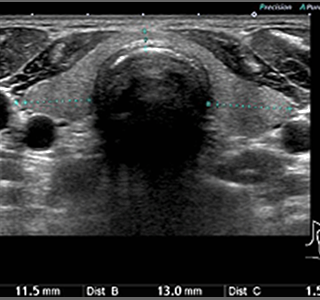

首の腫れや甲状腺の検査に使用いたします。この検査は無痛で行うことができ、かつ首の腫れの原因を検索することに優れています。また、甲状腺疾患の診察・定期検査としても使用します。

くびの腫れについて

首にはリンパ節が多数存在しており、咽頭炎などの炎症や腫瘍性病変によって腫大することがあります。また、甲状腺疾患が原因であることもあります。

当院では触診の後、必要に応じて超音波検査(エコー)による頸部のリンパ節や甲状腺を精査することが可能です。